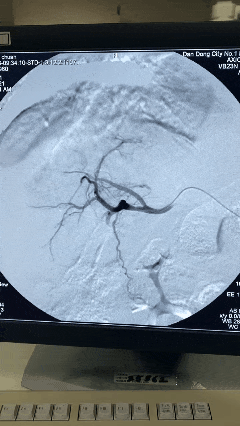

栓塞后DSA显示肿瘤出血完全停止